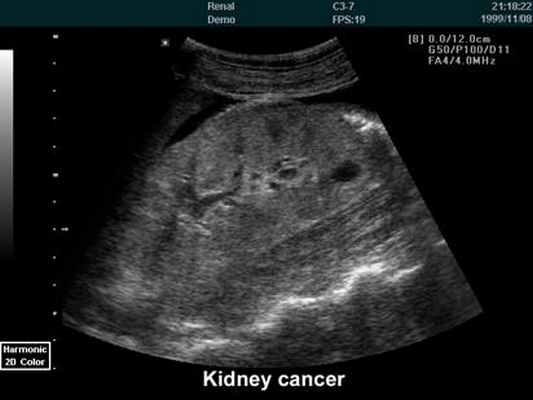

При проведении УЗИ врач оценивает выраженность диффузных изменений

почечной паренхимы, выявляет кисты, доброкачественные и злокачественные опухоли. УЗИ информативна